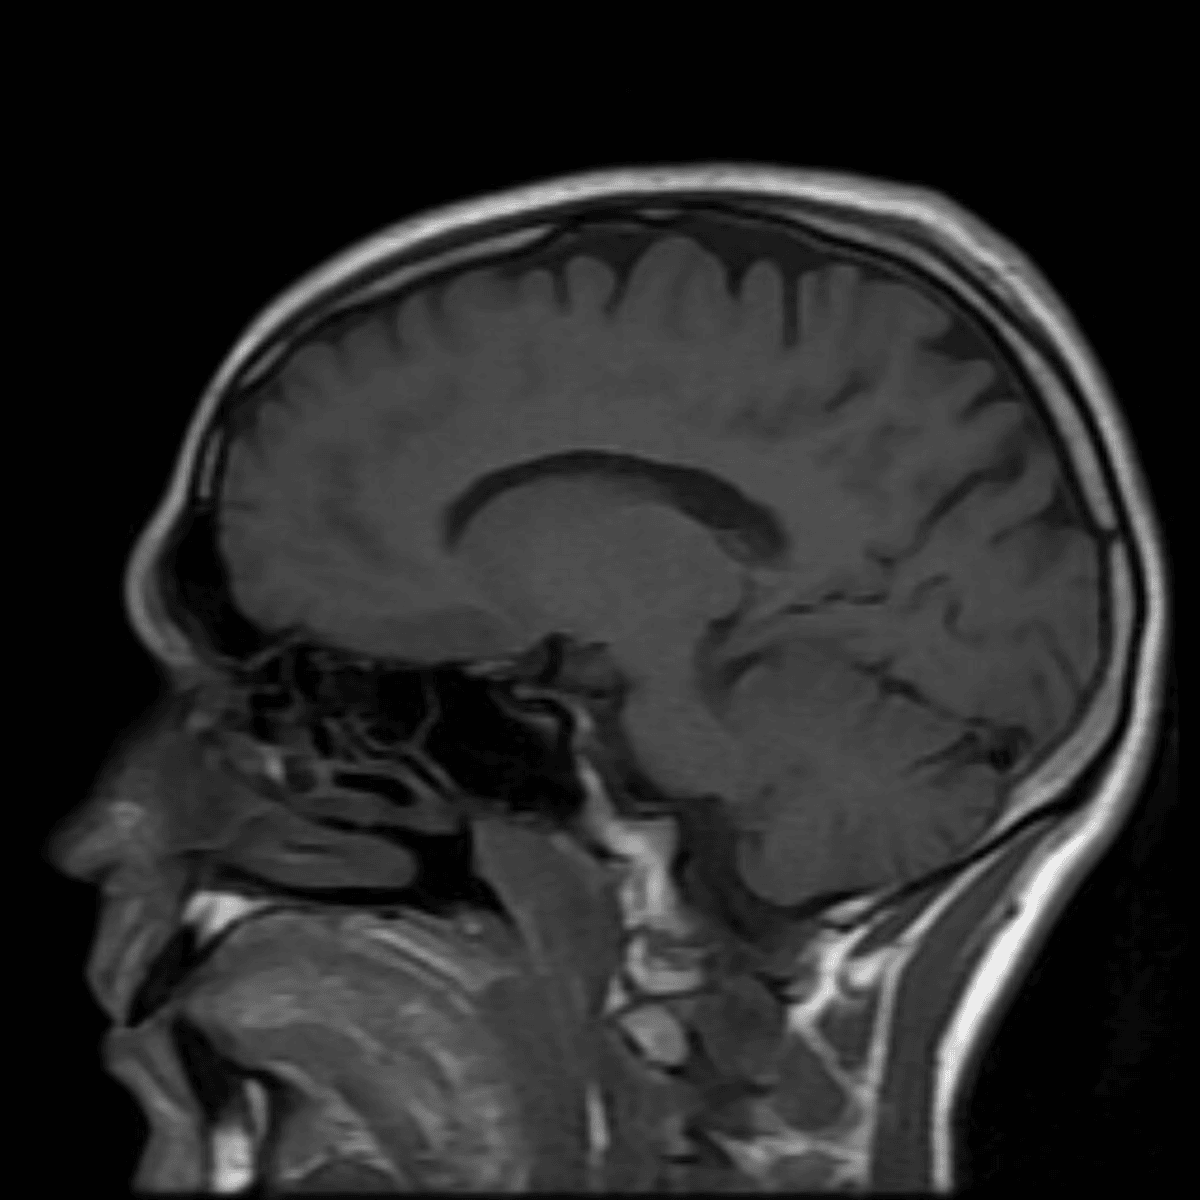

The heart has 4 main chambers - 2 atria, one that receives blood from the body and another from the lungs, and 2 ventricles, one which pumps blood to the body and the other to the lungs. The left ventricle appears enlarged (hypertrophy). Causes of left ventricle enlargement include: βnormalβ athleteβs heart, high blood pressure, aortic valve stenosis and hypertrophic cardiomyopathy.